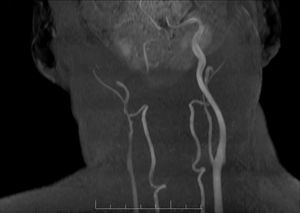

We present the case of a 49-year-old man with history of chronic obstructive pulmonary disease and category C3 HIV infection (CD4 count of 140 cells/mm3), diagnosed 3 months prior to admission. He was receiving regular treatment with bictegravir, emtricitabine, and tenofovir alafenamide. The patient reported right frontoparietal headache of 6 months’ progression, which led to several visits to the emergency department, where a head computed tomography (CT) scan was performed, revealing no alterations. He progressively developed diplopia and photophobia. The neurological examination revealed fluctuating ptosis, hyporeactive mydriatic pupil, and diplopia in all directions of gaze, with limited infralevoversion, levoversion, and supraversion, all involving the right eye. No meningeal signs or fever were observed. A brain MRI study revealed a contrast-enhancing mass in the right cavernous sinus, extending to the orbital apex and affecting the wall of the right internal carotid artery (Fig. 1). A routine biochemical analysis and blood count detected no relevant abnormalities. Cerebrospinal fluid (CSF) analysis revealed no red blood cells, 3 nucleated cells, lactate level of 8.8 mmol/L, protein level of 0.37 g/L, and glucose level of 0.47 g/L; adenosine deaminase levels were normal. A chest, abdomen, and pelvis CT scan revealed no pathological findings. Serology for toxoplasma, syphilis, and Borrelia, and a PCR test for cytomegalovirus yielded negative results. Gram staining and CSF culture for bacteria and mycobacteria also returned negative results. Testing for the galactomannan antigen and (1-3)-β-d-glucan and PCR test for Aspergillus yielded negative results in serum and CSF. PCR testing did not detect Pneumocystis jirovecci, Cryptococcus neoformans, or Histoplasma capsulatum in the CSF. A biopsy specimen of the lesion was obtained through the endoscopic endonasal transsphenoidal approach. Gram staining, cultures, and PCR testing of the specimen yielded negative results for fungi and bacteria. A histological analysis revealed an inflammatory lesion with abundant histiocytes, neutrophils, and fungal colonies suggestive of Aspergillus spp. Based on the anatomical pathology results, we collected a sample to repeat the PCR test, which finally yielded positive results for Aspergillus spp. We administered a 2-week course of intravenous antifungal treatment with voriconazole at 6 mg/kg every 12 hours during the first day, followed by 4 mg/kg every 12 hours and liposomal amphotericin B at 4 mg/kg every 24 hours. Amphotericin was switched for intravenous caspofungin at 50 mg/kg due to impaired renal function and hyponatraemia. Voriconazole was suspended after 10 days due to hepatotoxicity, and we started oral posaconazole at 300 mg daily at discharge. Antiretroviral therapy was not modified. At a 5-month follow-up visit, we observed good clinical progression, with the patient being asymptomatic. From a radiological viewpoint, the patient was stable, with the follow-up MRI scan showing no changes.

Aspergillus fumigatus is the most frequent cause of aspergillosis in humans. Although it mainly affects immunocompromised patients, its incidence is low in patients with HIV, and is usually limited to those with a CD4 cell count below 100 cells/mm3. In 80% of cases of invasive aspergillosis in patients with HIV infection, the lesion is located in the lungs; involvement of the cavernous sinus is rarely reported.7–9 Brain MRI is the most useful tool for diagnosing the condition, although a definitive diagnosis is not always reached.1,10 Cavernous sinus involvement is typically characterised by heterogeneous, hypointense lesions on T1- and T2-weighted sequences, as well as a tendency to invade nearby vessels, as in our case, in which we observed involvement of the internal carotid artery (Fig. 2).11–13 Laboratory tests are usually inconclusive.14 Testing for galactomannan antigen and (1-3)-β-d-glucan in the serum and PCR testing for Aspergillus are useful tools, although sensitivity may be affected in cases with sinus involvement.9 In our case, the first PCR test of the biopsy specimen yielded negative results; therefore, obtaining a specimen for histological analysis was essential for management and definitive diagnosis. However, collection of the specimen was limited by the patient’s clinical status and the delicate anatomical location.